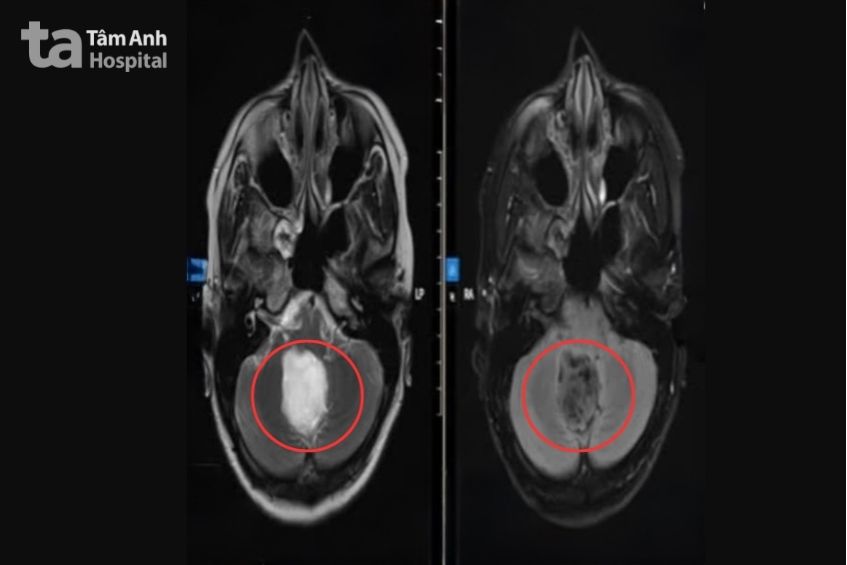

Tiếp nhận bệnh, ThS.BS.CKII Chu Tấn Sĩ, Trưởng khoa Ngoại Thần kinh – Cột sống, Trung tâm Khoa học Thần kinh nghi ngờ các triệu chứng cho thấy chị Trang có tổn thương thần kinh trung ương, chỉ định chụp cộng hưởng từ MRI 3 Tesla có tiêm thuốc tương phản. Kết quả cho thấy một khối choán chỗ dạng nang, kích thước khoảng 4 cm ở vùng lỗ Magendie, hố sau, nằm sát thân não. Khối u đã gây chèn ép thùy nhộng tiểu não và mặt sau thân não, làm hẹp đường lưu thông dịch não tủy, gây giãn nhẹ hệ thống não thất.

Sau phẫu thuật, chị Trang tỉnh táo, tiếp xúc tốt, sức cơ tay trái cải thiện. Hình ảnh CT sọ não hậu phẫu ghi nhận khối u đã được lấy trọn, các cấu trúc não trở về vị trí bình thường, tụ khí và dịch trong hố sau lượng ít. Một tuần sau ca phẫu thuật, chị hồi phục ổn định, lưu viện theo dõi và bắt đầu tập vật lý trị liệu, phục hồi chức năng. Dự kiến sau khoảng ba tuần, chị có thể trở lại sinh hoạt bình thường và được tái khám định kỳ để theo dõi nguy cơ tái phát u não.